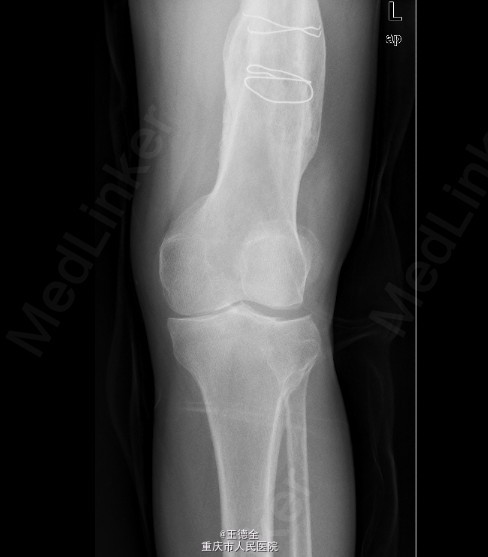

患者男,40岁,因“左股骨下段骨折术后4+年,左膝反复肿痛2年余”入院;自诉于4年前不慎被石块砸伤左大腿,伤后即觉左大腿疼痛,流血,左下肢活动障碍,患者伤后即到当地医院就诊,诊断为:"左股骨下段开放性骨折",予骨折切开复位内固定术,术后3个月下地行走,术后内固定螺钉松动、脱落,近两年来出现左膝关节肿胀、疼痛,活动时肿胀、疼痛症状加重,无畏寒发热、肢端麻木等,患者病后曾到当地医院就诊,予服药治疗后症状无明显好转,为进一步诊治遂来我院就诊,门诊拟"左膝骨性关节炎"收住我科,病程中,患者一般情况尚可,睡眠、饮食可,大小便正常,体重无明显改变。

查体:生命体征平稳,心肺腹未见异常;膝关节周围课件明显肿大,左膝关节活动受限,皮温略高;左股骨下端可扪及肿大,腘窝有一处大小约5x4cm的肿块,辅查x线片如下。